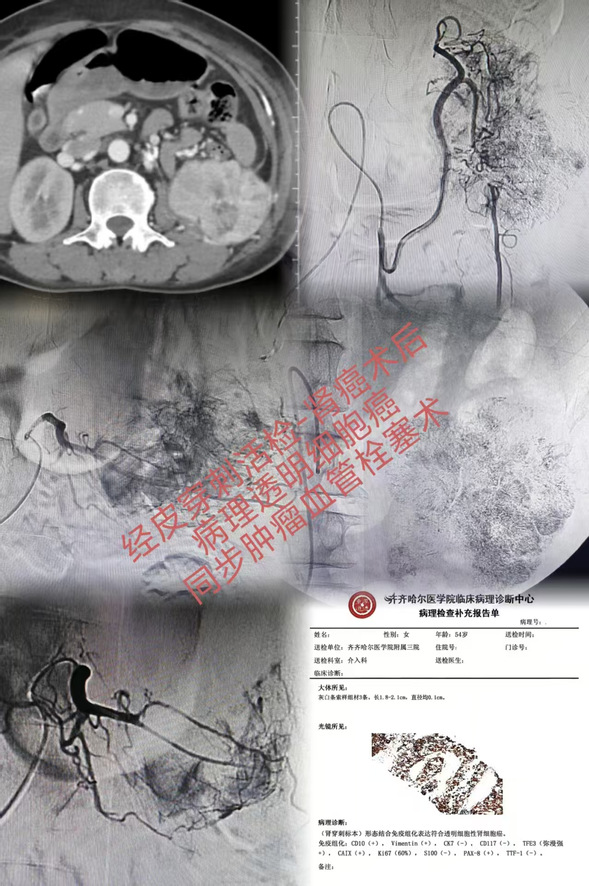

肾癌术后肾穿刺活检-病理透明细胞癌

取得精准的病理诊断并非终点,而是高效治疗的起点。介入医学最突出的优势,在于打破了传统诊疗中“诊断”与“治疗”的环节壁垒,率先启动“诊断+治疗”一体化介入方案。对于肾癌术后复发及富血供的肝癌,在完成活检确诊的同时,同步实施了肿瘤血管化疗栓塞术。这样一来,很大程度上减少了患者的创伤与等待时间。